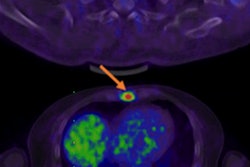

Prostate cancer comes in three distinct molecular subtypes, each of which correlates with distant metastasis-free survival, according to a presentation at the American Society for Radiation Oncology (ASTRO) meeting in Boston.